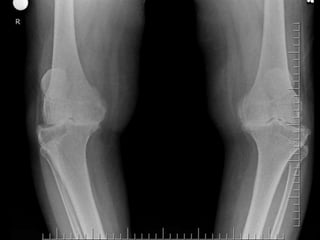

Normally, there is valgus alignment of 5 to 8 degrees in

the tibiofemoral angle as measured on radiographs taken in

the weight-bearing position. The amount of correction of the

arthritic knee needed to achieve a normal angle is calculated,

and an additional 3 to 5 degrees of overcorrection is added

to achieve approximately 10 degrees of valgus. With a varus

deformity, the only limitation in the amount of correction

from a valgus osteotomy is the size of the bone wedge that

can be taken proximal to the patellar tendon.